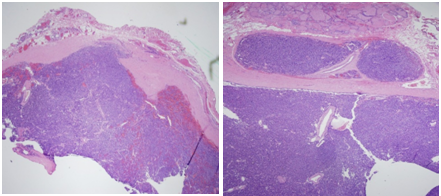

Neck ultrasound (Figure 1A & 1B) revealed a right dominant 2.8cm complex, solid and cystic nodule with intranodular and peripheral vascularity. She was admitted and was treated with intravenous (IV) normal saline. She received 1 dose of IV pamidronate 60mg. Her calcium level improved to 9.8mg/dl and was subsequently discharged. She underwent biopsy of the right thyroid nodule, which was consistent with parathyroid neoplasm possibly adenoma with immunohistochemistry negative for Thyroglobulin, TTF 1, Calcitonin and S 100. She was subsequently referred to endocrine surgery for evaluation of parathyriodectomy. CT scan of neck with 3D imaging reconstruction2 (Figure 2) study confirmed a large well defined nodule with peripheral enhancement suspicious for large right parathyroid adenoma. She underwent minimally invasive parathyriodectomy with fluid aspiration and intra-operative PTH levels fell from 289 pg/ml to 15.8 pg/ml. Pathology (Figure 3) was supportive of the diagnosis of atypical parathyroid adenoma with fragments of hyper cellular parathyroid neoplasm consisting of neoplastic cells with solid nest and trabecular growth patterns with focal capsular distortion and increased mitotic activity. Immunohistochemistry revealed Ki-67 proliferation index 1-3%, bcl-2 positive, diffuse strong and focal weak positive p 53. Post operatively; she was started on calcium and vitamin D supplementation. She is doing well and remains normocalcemic for 2 years following surgical resection with most recent calcium of 9.3mg/dl.

Figure 3 Hyper cellular neoplastic cells with solid nest and trabecular growth pattern separated by thick fibrous tissue band.